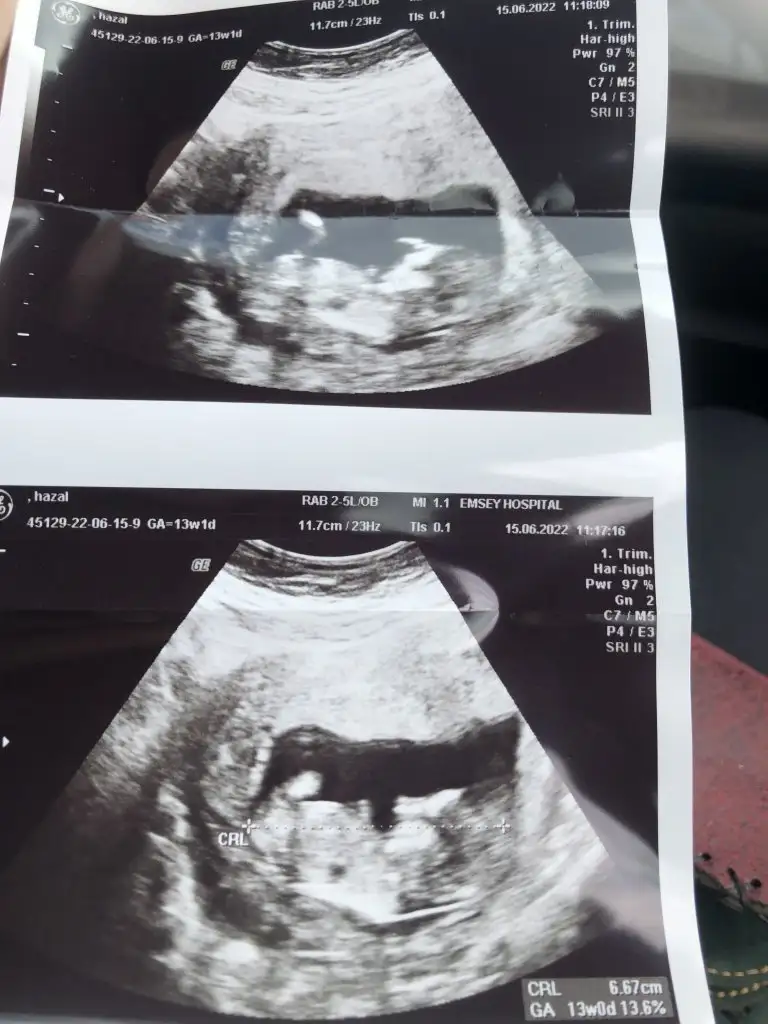

prenses gibiMerhaba bana da tahminde bulunur musunuz 11+2 de karından çekildi teşekkürler :)

Teşekkürlerpaşa gibi

Teşekkür ederim doktor da kız gibi dedi ama daha 20 gün sonra kesinleşir dedi kesinleşince yazarım mutlaka :)prenses gibi